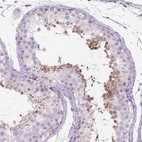

Immunohistochemistry analysis in human testis and endometrium tissues using Anti-C20orf144 antibody. Corresponding C20orf144 RNA-seq data are presented for the same tissues.